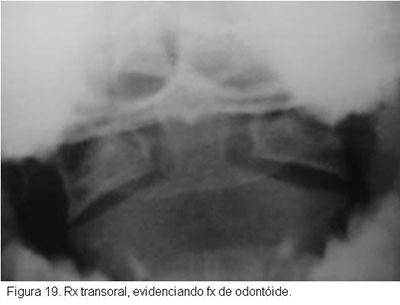

No estudo radiográfico, nas fraturas sem desvio, seja na projeção ântero-posterior, seja na de perfil, apenas se verá o traço de fratura do dente do áxis, e nas fraturas com desvio será vista a fratura com desvio do fragmento distal e o escorregamento do atlas. Nas fraturas sem desvio por vezes é muito difícil que se veja o traço de fratura, só sendo possível o diagnóstico pela tomografia.

Ainda quanto ao diagnóstico radiológico das fraturas sem desvio deve-se acrescentar que carece haver cuidado especial com as crianças, quando ainda não ocorreu ossificação completa da vértebra.Radiologicamente, na criança, o dente e o corpo do áxis estão separados por uma faixa de tecido transparente ao raio X, que progressivamente vai estreitando, até desaparecer aos 10-11 anos, quando o dente e o corpo do áxis se fundem, o que raramente não se completa em idades maiores. A não fusão do dente do áxis pode simular uma fratura sem desvio. Os pacientes com fratura do dente do áxis freqüentemente têm queixas pobres, apenas de cervicalgia pouco intensa e certa dificuldade para a movimentação do pescoço, não raramente procurando tratamento vários dias depois do acidente. Algumas vezes procuram tratamento referindo dor violenta, grande dificuldade à movimentação e suportando a cabeça com as mãos. Sinais neurológicos só aparecem numa pequena minoria (Figuras 18,19 e 20).